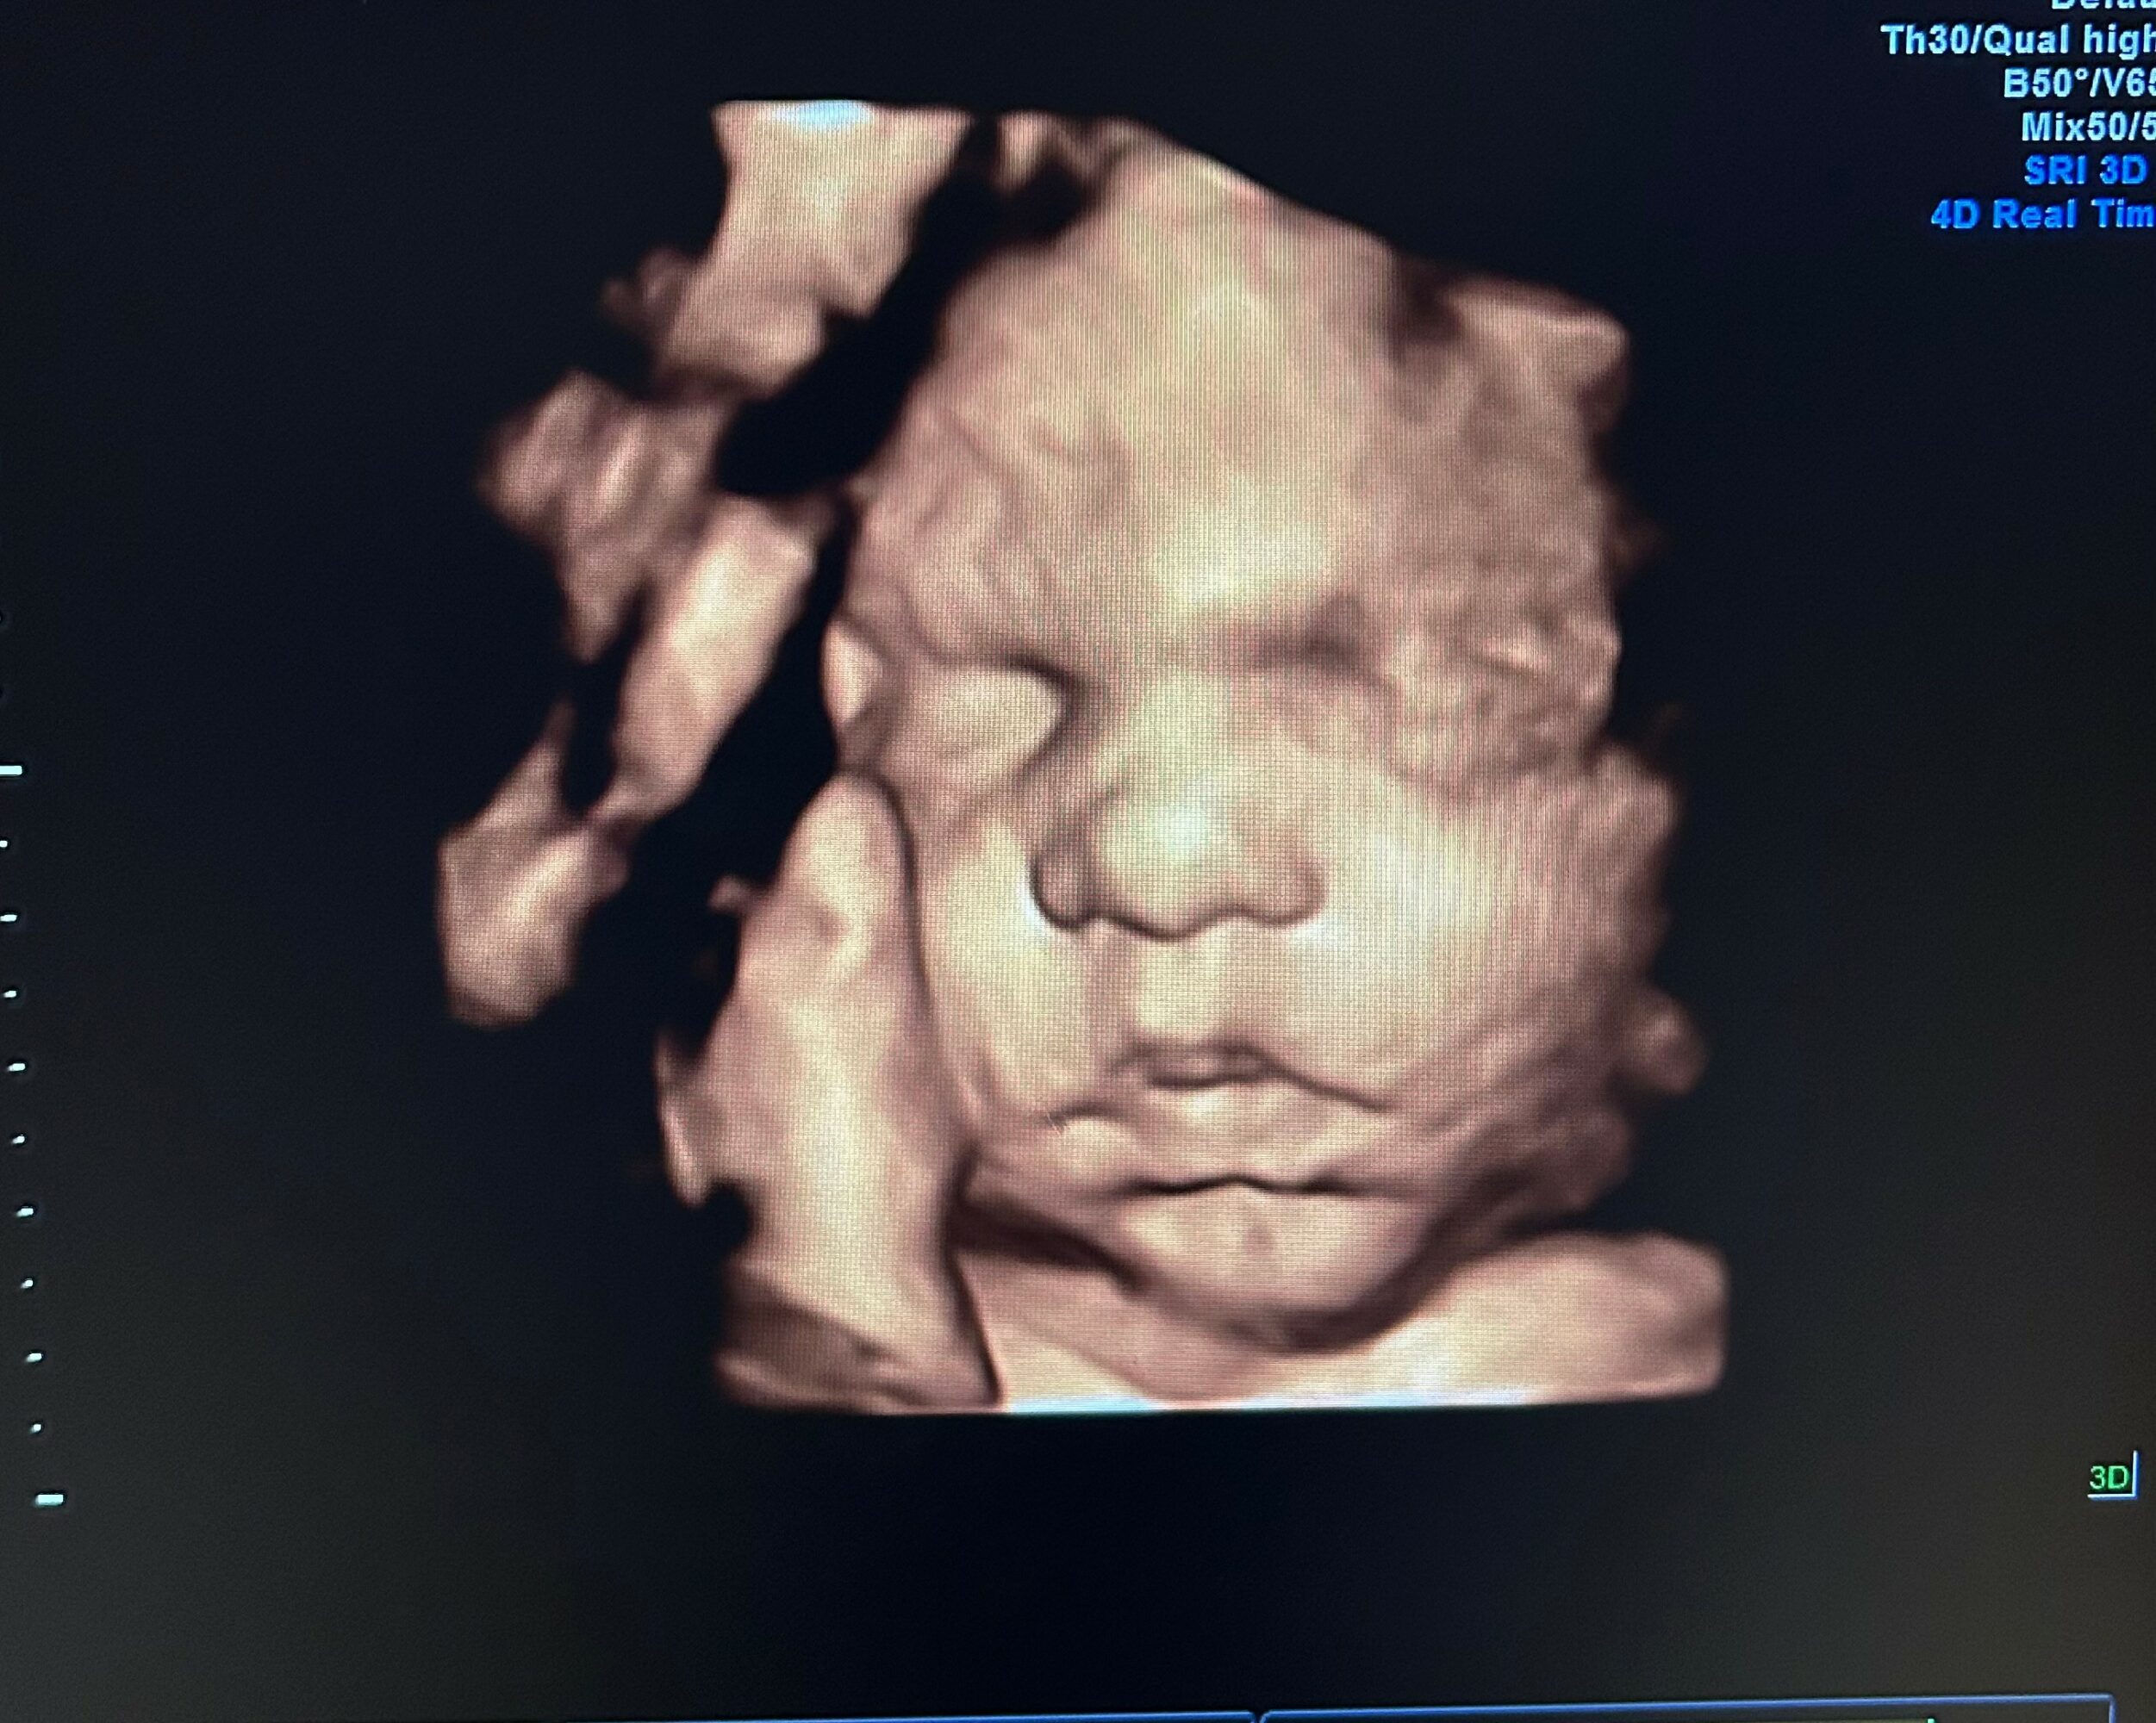

At Baby’s Image, we specialize in providing 2D, 3D, 4D, and HD live elective ultrasounds that allow families to bond with their babies long before delivery day. With nearly 18 years of experience as a registered sonographer, I bring a deep love for this profession and a commitment to creating a joyful, meaningful experience for every family who walks through our doors.

What we do goes far beyond imaging we create moments. We celebrate life. We help families experience the wonder of seeing their baby yawn, stretch, smile, or wiggle for the very first time. Those reactions the tears, the laughter, the awe are what make this work so special to us.

We are also proud of the atmosphere we’ve created warm, peaceful, and family centered. Whether it’s an early peek, a gender reveal, or watching baby grow throughout pregnancy, we strive to make every visit memorable. Many clients have told us their experience at Baby’s Image feels personal, comforting, and unlike anywhere else they’ve been and that is one of the greatest compliments we could receive.